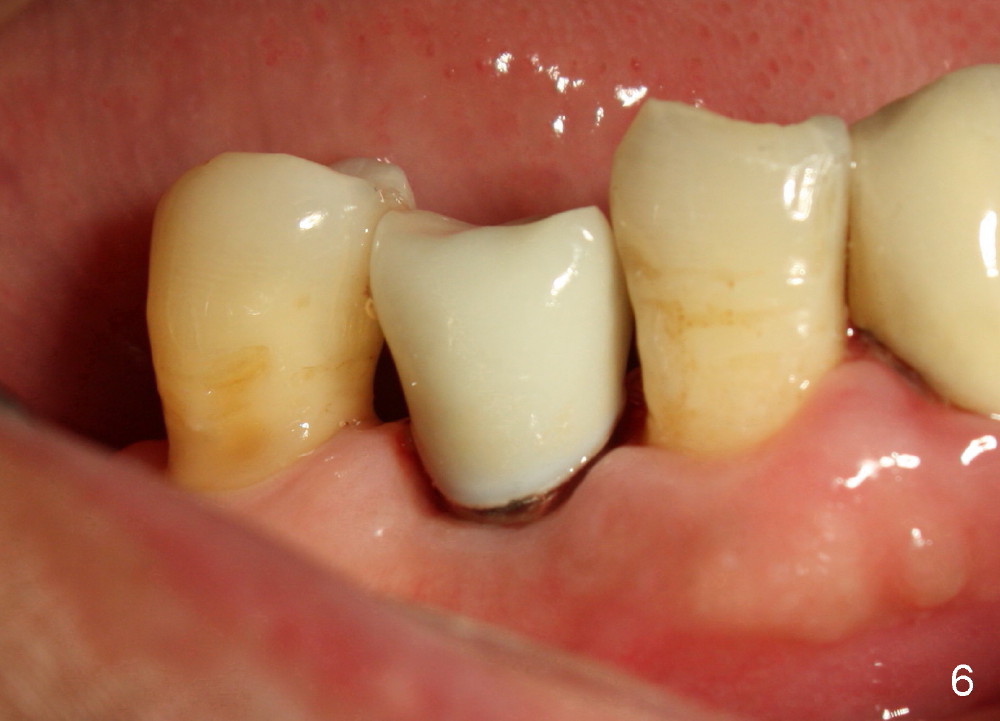

A 66-year-old man has poor dentition (Fig.1). Several teeth (x) including #28 need extraction and implants. The tooth #28 is extracted (Fig.2), followed by immediate implant (5x17 mm, Fig.3 I). There is more buccal gingival recession over the implant (Fig.4), which is less prominent 1.5 months postop (Fig.5). The definitive restoration is delivered less than 2 months postop (Fig.6), because of travel abroad. The patient agrees not to chew with the Emax crown. Five months later, he returns with chipped porcelain (Fig.7 arrowhead). It appears that immediate implant can survive early and over loading. More implants are necessary to share the masticatory loading. Since there is malocclusion, where to place implants appears to be critical (Model 3 30 4 5 6 7). There is no bone loss 4.5 years (Fig.8) or 5 years 8 months (Fig.9) post cementation.